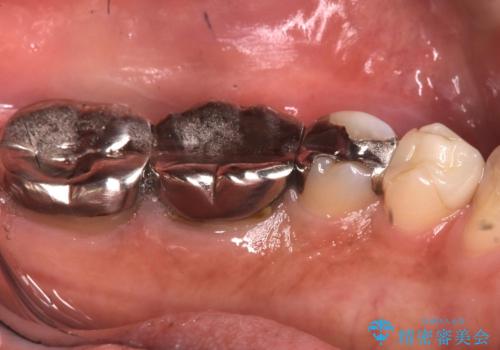

メタルインレーを除去したところ、二次カリエスうを確認したため除去・CR裏層の後、形成・印象しています。

セラミックインレーの接着操作時にはラバーダム防湿を行っています。